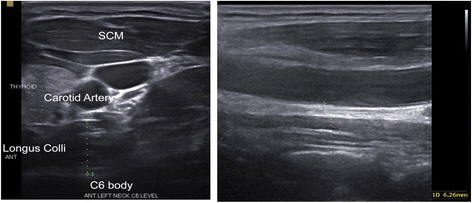

Temporal Ultrasound first

I was allowed to watch the ultrasound fully and I have a good understanding of what I watched unfold but I am not a medical professional and will await the report.